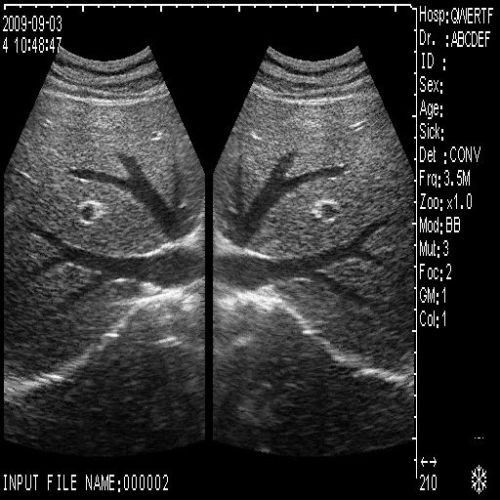

image: +3D High clear

Probe Function: 3.5MHZ convex, abdominal organs

The Ultrasound Scanner is a state-of-the-art device designed for comprehensive pregnancy imaging. It features both convex and transvaginal probes, allowing healthcare professionals to obtain detailed images of the fetus and surrounding structures. This dual-probe system enhances diagnostic accuracy, making it easier to monitor the health of the unborn child. Expecting mothers benefit from these advanced imaging techniques, enabling early detection of potential complications.

The importance of the Ultrasound Scanner in modern medicine cannot be overstated. By combining advanced technology with ease of use, this tool significantly improves diagnostic accuracy. As a result, healthcare professionals can identify any abnormalities earlier, leading to timely interventions. Additionally, the profound impact on patient care is evident, as clearer images and better diagnostics translate to enhanced outcomes for both mothers and their babies.